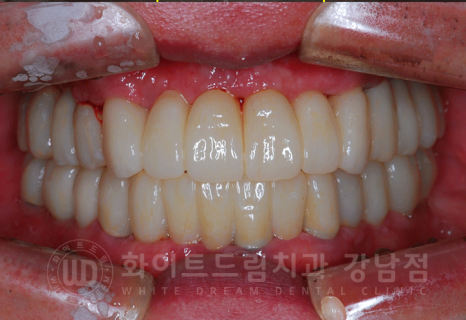

총 치료 기간 2017.06.03 - 2018.02.21 8개월 소요.

동일 인물이며 동일 환경에서 촬영되었습니다.

전악 임플란트는 낮아진 교합을 다시 설정하는 교합 거상술이 필요하기 때문에

보통 1년 정도의 기간을 두고 치료를 진행합니다.

치주염이 심해 거의 모든 잇몸뼈에 염증이 있는 상태였는데

3D CT를 통해 단단한 잇몸뼈 부위를 찾아 식립했으며, 1년 이내의 치료 기간이 소요되었습니다. ^^

환자분도 치료 기간 내내 적극적인 협조를 해주셔서 보다 빠르게 치료가 완료된 것 같습니다.